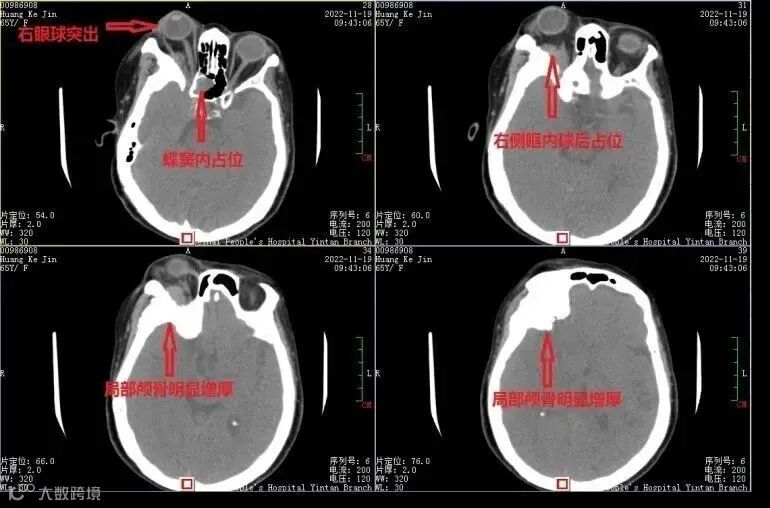

术前ct

11月下旬,患者因右侧眼球突出,在市人民医院眼科就诊,检查发现鼻窦里也有肿物,收住耳鼻喉科,磁共振检查又发现颅底生长有肿瘤,做了鼻窦肿物活检,确定是个脑膜瘤,由于眼眶、鼻窦、颅内都有肿瘤侵犯,12月6日,患者转入神经外科。

术前磁共振检查更清楚显示颅内及右侧眶内、蝶窦内广泛侵袭,局部颅骨增生明显。